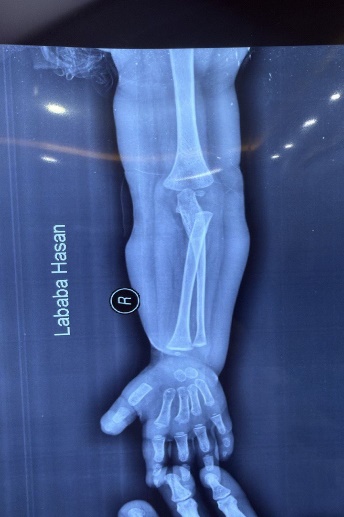

Skeletal: Short broad hands/feet, clenched fists, bilateral clubfoot.

Our patient’s manifestations—severe hypotonia, seizures, craniofacial dysmorphism, cortical blindness, and skeletal deformities—are consistent with previously reported PIGV-related cases [4,6,10]. Congenital heart disease (ASD) has occasionally been described in this subtype [7,11].

Figure 11: Skeletal deformities of the upper and lower limbs

Photographs showing short, broad hands with clenched fingers (upper image) and bilateral clubfoot deformities (lower image), consistent with skeletal abnormalities described in HPMRS.